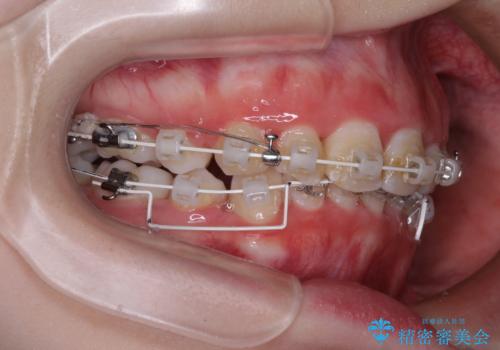

- 矯正装置

- 審美装置

ディープバイトは、治療を行っていた我々も驚くほど、短期間で劇的に改善することができました。

骨格的に下顎骨が左側にシフトしていたため、上下正中の位置や左側臼歯部の咬合を理想的に仕上げることはできませんでしたが、非常に綺麗な口元を達成することができました。